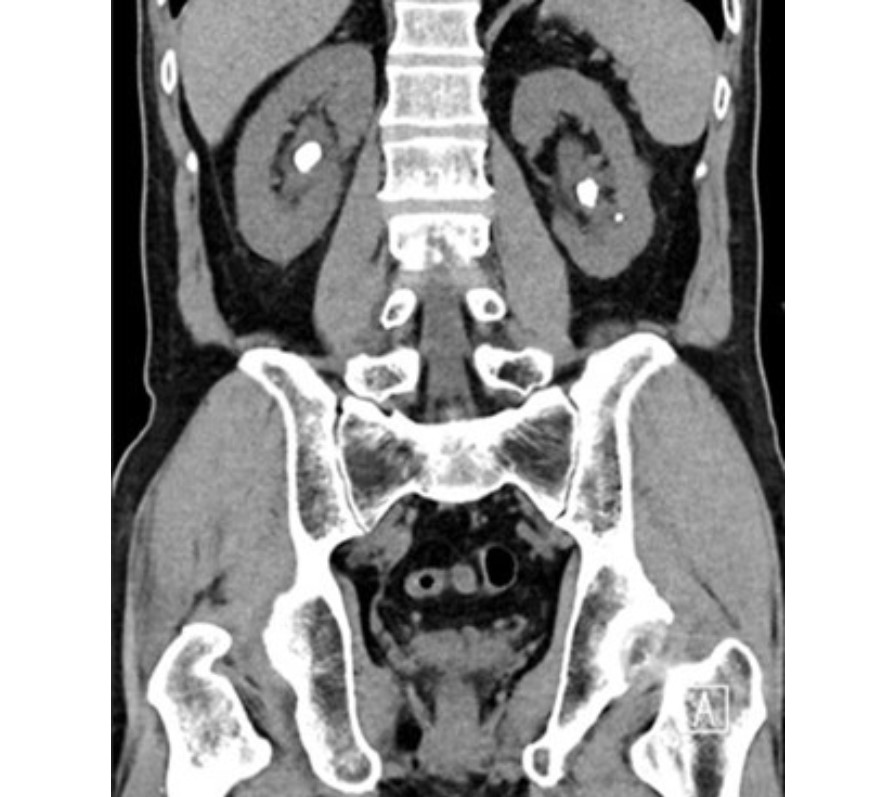

Your doctor may order imaging, including X-rays or a CT scan to diagnose kidney stones. These would help to determine the size and location of the kidney stones, and whether the stones are causing any obstruction. Urine and blood tests may also be ordered to assess if there is concurrent urinary tract infection and whether kidney function is affected by the kidney stones.

Figure 1: CT scan with kidney stones